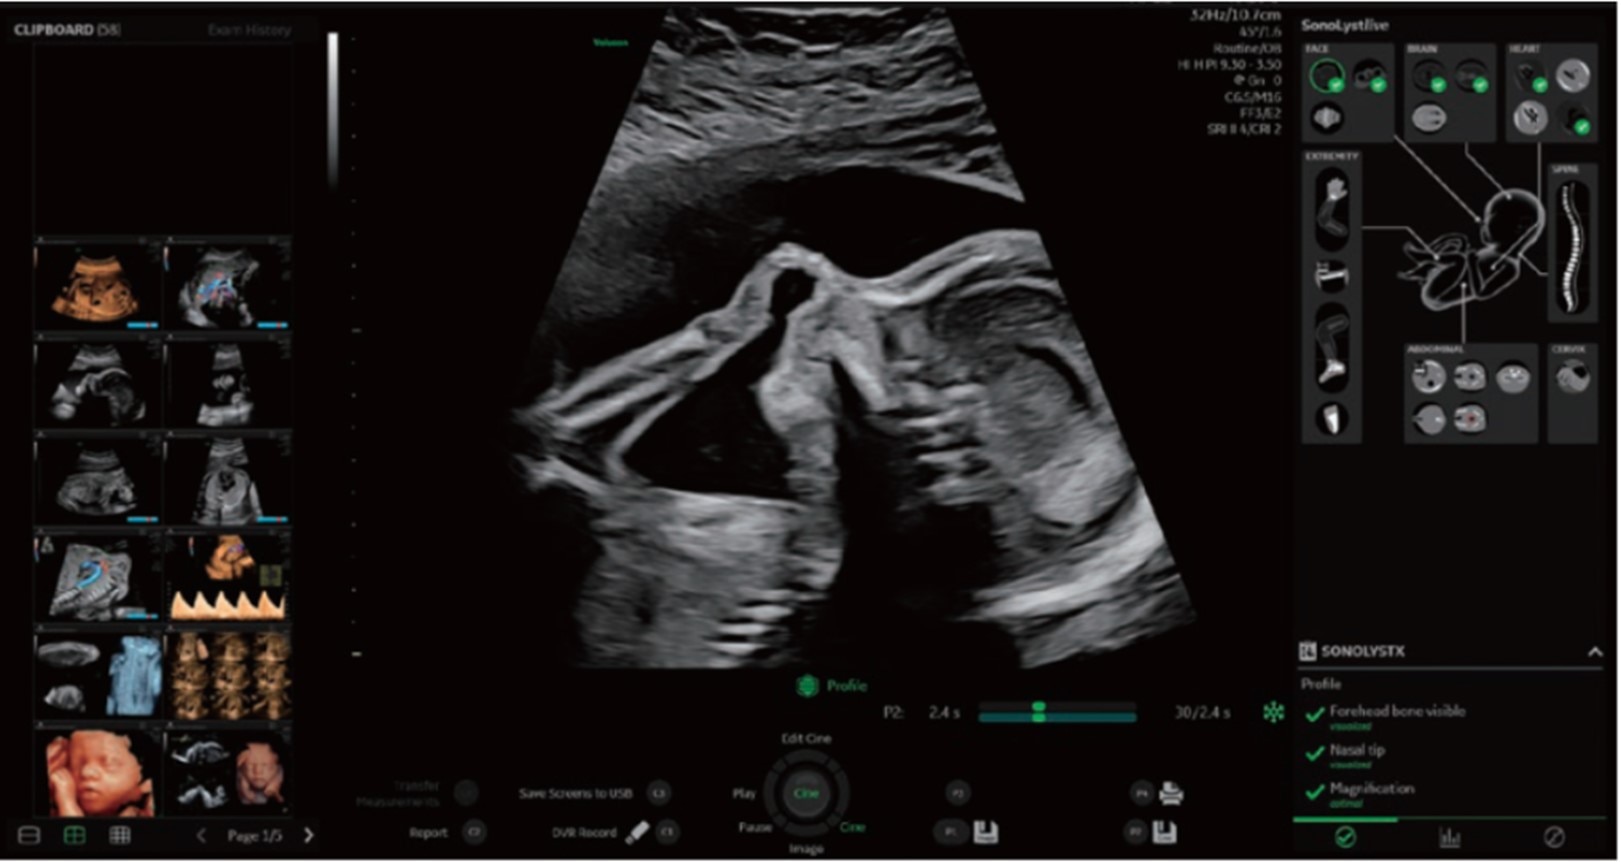

■ 検査の質と効率向上を支援するクリニカルツール:SonoLyst

SonoLystは、ワークフロー改善のためにAI手法を用いて開発されたソフトウェアです。ISUOG(国際産婦人科超音波学会)ガイドラインに準拠し、解剖学的な特徴からスキャン中の描出断面が基準断面にどれほど近づいているかを知らせて医師のスキャンをサポートします。フリーズ後は、ガイドラインの基準断面に即したどの部位であるかを自動認識し、ユーザーに提案し、ユーザーがそれを受け入れると、チェック済項目として保存されます。これにより、胎児スクリーニング検査の効率化と検査クオリティの担保、ユーザーの自己学習の推進に貢献します。

SonoLystを用いた検査画面